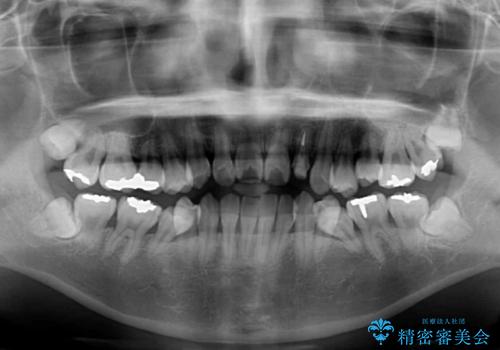

- 下顎の歯が舌側に倒れていることと、前歯の咬み合わせの不具合を気にして来院された患者様です。

受け口傾向の口元であるため、下顎左右小臼歯各1歯を抜歯して歯列を整えることとしました。

前歯には治療中の仮歯が装着されていたため、矯正治療後にオールセラミッククラウンにて補綴治療を行うこととしました。

抜歯矯正は2年から2年半程度の治療期間を要することが一般的ですが、僅か1年1ヶ月で終了しました。